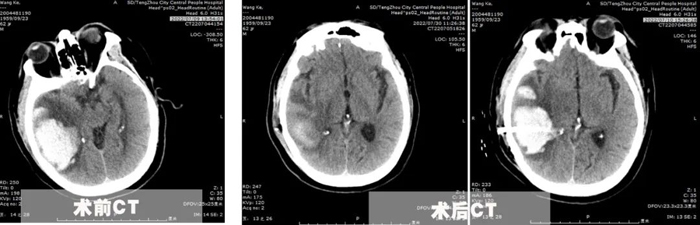

患者王先生,62歲,體重200余斤,糖尿病、冠心病、腦梗塞病史3年余,長期口服二甲雙胍、阿司匹林、瑞舒伐他汀等藥物,病情控制一般。7月8日,患者突發(fā)頭痛頭暈,出現一側肢體偏癱、意識障礙,急診行顱腦CT提示枕頂葉大面積腦出血,血腫量超過50ml,有手術指征。

為了在最恰當的手術時機及時完成手術,7月10日,李永濤主任放棄在家休息的時間,帶領陳凡宇主治醫(yī)師,在局麻下為患者完成顱骨鉆孔腦出血引流術。術中僅在切口線注入5ml利多卡因,然后顱骨鉆孔形成直徑約1cm骨孔,切開硬腦膜后精準置入直徑約5mm的硅膠引流管于血腫腔,術后復查CT并引流管內注入尿激酶促進血腫引流。經過3天的引流,血腫基本排除,腦壓下降,癥狀改善。同時盡早給予患者床旁肢體功能康復,并積極調整患者血糖、血壓、及心臟功能,給予患者精神鼓勵和心理輔導?;颊叱鲈旱臅r候已經能夠獨立行走,生活自理。